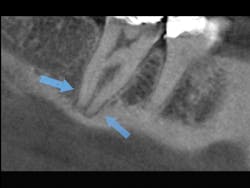

General dentists accomplish the vast majority of endodontic treatment in the United States. This treatment is reported to be the third most frequent use of cone beam. Endodontists, who are the leaders and teachers for endodontic treatment, are now using cone beam routinely. What are some of the reasons for this use? All of us occasionally have a patient with an endodontically treated tooth that appears on a 2-D radiograph to have received excellent endodontic treatment, but the patient still has discomfort. You know the various potential reasons for this treatment failure, but can you visually determine them? Is the tooth cracked? Is there another root or another canal that you cannot see on a 2-D image? Do overlapping roots disguise a problem or condition that could easily be seen on a 3-D image (figures 4-6)? It is easy to predict that cone beam will soon become recognized as being necessary for predictable endodontic diagnosis and treatment.

Figures 4-6: These images provided by Dale Miles, DDS, MS, show a lower right second molar with multiple roots. It is apparent that a 2-D view would be inadequate to provide enough information for appropriate endodontic treatment.